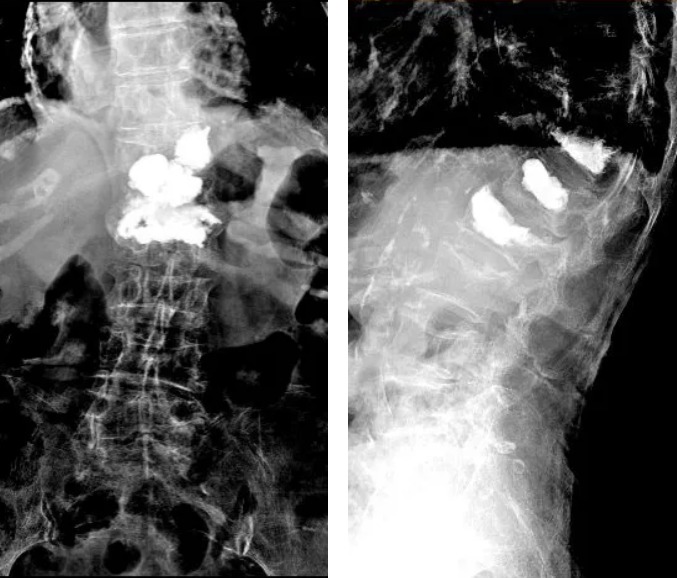

手术后复查的X线片

手术结束后,张奶奶立刻感觉到疼痛大幅度的缓解,术前稍微挪一挪身体都会引起剧烈疼痛,术后立刻就能自行翻身了,效果十分明显。手术后复查的X线显示骨水泥弥散良好。术后1周,张奶奶已经完全可以自己下地走路了。